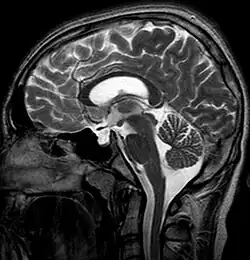

The empty sella sign is a radiological finding characterized by the partial or complete filling of the sella turcica with cerebrospinal fluid (CSF), causing the pituitary gland to appear flattened or compressed against the walls of the sella.[1] This results in the sella appearing "empty" on imaging, despite the presence of a compressed pituitary gland. The empty sella sign is typically identified on magnetic resonance imaging (MRI) or computed tomography (CT) and can be associated with various clinical conditions or incidental findings.[2]

MRI is the gold standard for diagnosing the empty sella sign. Key features include:[5]

- CSF signal: The sella turcica is filled with material that follows the signal characteristics of CSF on T1-weighted and T2-weighted images.

- Flattened pituitary gland: The pituitary gland appears thin and plastered against the sellar floor or walls.

- Enlarged sella: The sella turcica may appear expanded or normal in size.

On CT, the empty sella sign may appear as hypodensity in the sella, corresponding to CSF. There may be possible sellar floor thinning or remodeling due to chronic pressure changes.